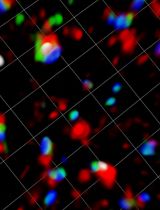

Figure 4. Dynamic intestinal microcirculation in neonatal mice. A. Intestinal microcirculation image obtained by TPLSM. B. Blood flow volume calculation. C. Blood vessel wall shear rate calculation. D. Leukocyte rolling speed calculation.

Blood flow volume

Blood flow volume (FV) is calculated using the following formula (Figure 4B and Figure 5):

FV [µm3/ms] = π(d/2)2ΔX/ΔT

[d] is the maximum diameter of the blood vessel

Shear rate of blood vessel wall

Blood vessel wall shear rate (W) is calculated in a 100-µm segment of the vessel using the formula based on the Newtonian definition (Russell et al., 2003) (Figure 4C and Figure 5):

W [1/ms] = 8V/d

Blood flow velocity

The blood flow velocity (V) is calculated as described in several studies that quantified the blood flow in vessels of different caliber, from arteries to capillaries (Tang et al., 2015). In one movie (20-30 s), select a sequence of the four to six most clear images of a blood vessel. Measure the tangent length that is parallel to the blood flow direction (ΔX) and the cosine length of the strand that is vertical to the blood flow direction (ΔT). The blood flow velocity is calculated using the following formula (Figures 4A, 4B and Figure 5):

V [µm/ms] = ΔX/ΔT

Velocity can be defined as a mean value calculated from four or six strands selected from the movie.